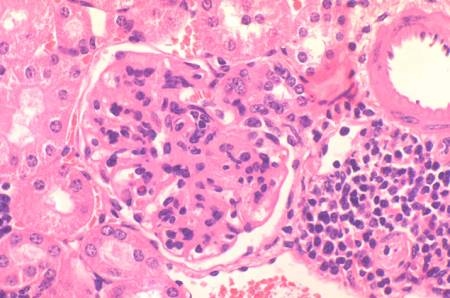

Numerosas enfermedades autoinmunes se caracterizan por la presencia de linfocitos B autorreactivos con capacidad para reconocer antígenos propios y ocasionar daños en los tejidos del individuo. Nuestro sistema inmunitario tiene diversos mecanismos para eliminar estas células autorreactivas que pueden ocasionar el desarrollo de enfermedades autoinmunes, como lupus eritematoso sistémico, artritis reumatoide, diabetes y esclerosis múltiple. Un estudio con participación del Consejo Superior de Investigaciones Científicas (CSIC) (España) y publicado en la revista Nature Immunology desvela un regulador clave en este proceso. Según los resultados de este trabajo, el aumento de expresión de la molécula micro ARN 148a (miR-148a) facilita la supervivencia de linfocitos B autorreactivos, que deberían ser eliminados, desencadenando así el desarrollo de lupus.

“La función de las proteínas Bim y PTEN para prevenir la autoinmunidad ya era conocida en el campo, sin embargo este estudio es pionero ha identificado por primera vez la función del gen supresor de autoinmunidad GADD45a en el control de la tolerancia central de linfocitos B. Los ratones deficientes en esta proteína desarrollan espontáneamente una enfermedad similar al lupus eritematoso sistémico” destaca Jesús Salvador.

Según el estudio, al aumentar la expresión de miR-148a en un modelo murino de lupus (proceso frecuente en pacientes con lupus eritomatoso o artritis reumatoide) el desarrollo de la enfermedad autoinmune se aceleró ocasionando la muerte prematura. “Conocer los mecanismos que controlan la autotolerancia puede llevar a nuevas estrategias para el tratamiento de la autoinmunidad”, concluye el investigador.